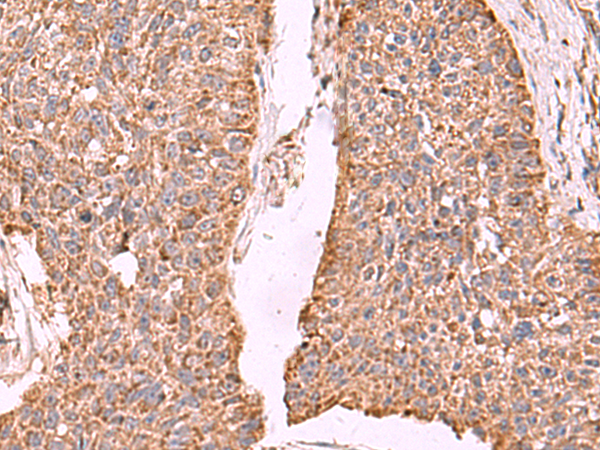

(Immunohistochemistry of paraffin-embedded Human esophagus cancer tissue using PER3 Polyclonal Antibody at dilution of 1:55(×200))